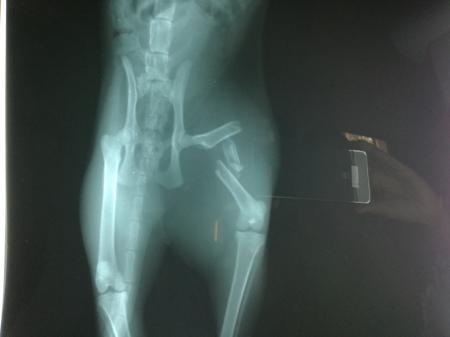

Hallo, gestern kam unsere gerade 1-jährige Krümel verletzt nach Hause, nachdem sie einen Tag verschwunden war. Wir merkten gleich, dass etwas nicht mit ihr stimmt. Dann der Schock: Als sie auf uns zugelaufen kam, baumelte ihr rechter Hinterlauf nur so an ihr rum, als ob er da nicht hingehört. Vermutlich wurde sie angefahren.Sie hat natürlich schwer gejammert und gefaucht. Fressen und Trinken ging normal. Heute früh sind wir mit ihr in die Tierklinik, Röntgenbild gemacht, Trümmerbruch! Es stand zur Wahl: Entweder "so lassen wie es ist, es wächst irgendwie zusammen", oder operieren. Wenn wir es so lassen, dann weiß man nicht wie es zusammenwächst und ob sie ihr Bein wieder normal belasten kann, geschweige denn schmerzfrei wäre...sie tat uns so leid, sie hatte ganz groß Pupillen und hat gejault vor Schmerzen. Wir haben uns für die OP entschieden und mussten sie gleich dort lassen, morgen wird sie operiert, Montag können wir sie wieder abholen. Ich hoffe, es geht alles gut. Der Doc meinte, er bringt einen Draht in den Knochen ein und "fädelt" die Bruchstücke auf, so dass sie wieder in einer Reihe stehen und vernünftig zusammenwachsen können. Heilung würde dann sehr schnell verlaufen, sie müsste rund 3 Wochen drinnen bleiben in einem Raum, wo sie nirgends hochspringen kann....Och mensch, ich vermiss die Kleine so, wenn ich mir vorstelle sie liegt grad in irgendeinem Käfig, an einem fremden Ort, fremde Tiere, fremde Menschen... Hat jemand schon eine ähnliche OP an seiner Katze gehabt und wie hat sie es überstanden? Wie lange hat die Heilung gedauert? Was hat die OP gekostet? LG Katharina

Ich frage mich gerade, wie DAS hätte irgendwie zusammenwachsen sollen ?

Tja, der Tierarzt meinte es gäbe da ein Sprichwort: "Wenn man eine Katze und einen Haufen gebrochener Knochen nebeneinander stellt, heilen die Knochen." Bloß wie halt....Egal, sie ist mittlerweile operiert, nachher müssen wir anrufen und mal nachhören wie es ihr geht, morgen früh darf sie dann wieder heim